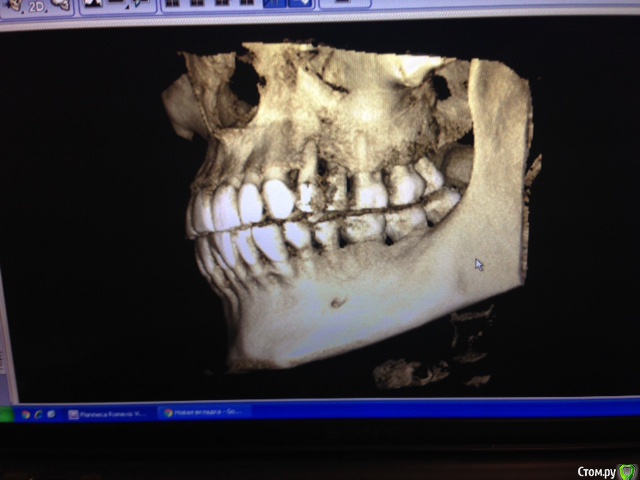

Hellae Опубликовано 17 января, 2016 Поделиться Опубликовано 17 января, 2016 Просьба откликнуться специалистов что делать в моей ситуации. У меня уже год шатается 4 зуб верхней левой челюсти. Длительное время постоянно кровил. Удалять сказали еще в феврале 2015, но я все никак не решалась т.к. вместе с ним требуется удаление еще и 5-го зуба рядом с ним. Плюс ко всему это связано с генерализованным парадонтитом(так мне сказали) на фоне которого и расшатался 4-й зуб. Сейчас имплантолог сказал надо удалить 2 зуба (4 и 5) подсадить костную ткань и ждать когда она приживется, потом ставить импланты, а пока кость нарастает сделать лоскутные операции.Снимки у мня только КТ февраль 2015 я сфотографировала панораму и прицельный двух зубов может можно как то по ним увидеть. Ссылка на комментарий